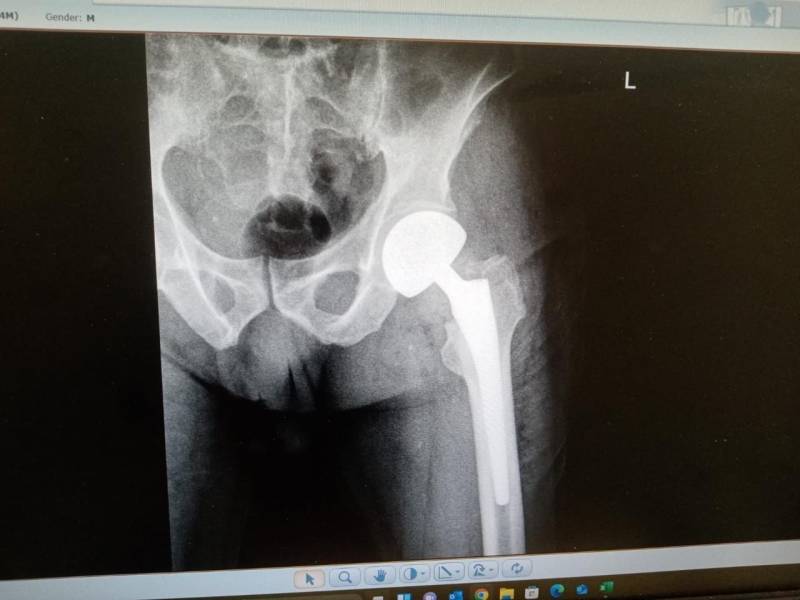

- إجراء عمليات جراحية معقدة و دقيقة في مجال العظام و المفاصل و الكسور و الإصابات ، رغم الضغط الكبير على المستشفى و أعداد المراجعين الكبيرة.

- تطبيق تقنيات جراحية حديثة و متقدمة، و ذلك في ظل التحديات التي يواجهها الفريق بسبب أعداد المرضى و المراجعين الكبيرة.